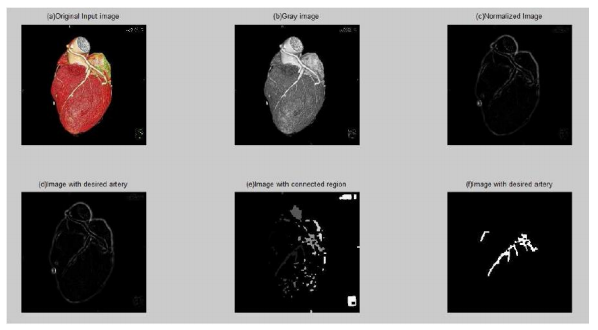

Calcification Detection in Coronary Arteries using image processing

Matlab

Technology Used : Matlab

Description: The source data is filtered two dimensional DICOM (Digital imaging & Communications in Medicine) images taken from the 64 Slice Computed tomography Scan Data of the heart using a filter to highlight only the coronary arteries regions.